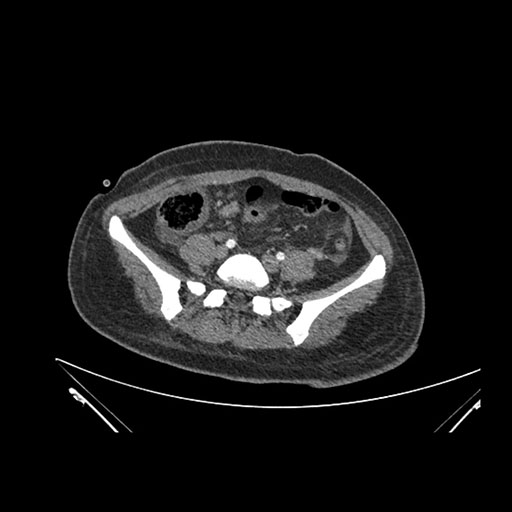

Coronal Venous

Imaging analysis

Based on initial findings, which issue(s) would you be most concerned about?